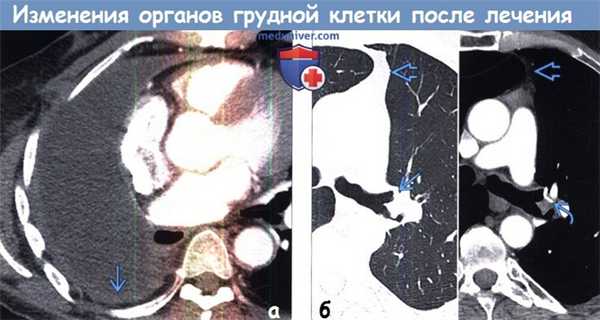

(а) Мужчина 58 лет, перенесший пневмонэктомию справа по поводу рака легкого. При КТ с контрастным усилением всю правую половину грудной полости занимает жидкость. Следует отметить доброкачественное утолщение париетального листка плевры справа.

(б) Пациент, перенесший верхнедолевую лобэктомию слева. На совмещенных изображениях при КТ с контрастным усилением в легочном (слева) и мягкотканном (справа) режимах визуализируются культя левого верхнедолевого бронха >i и хирургические скобы. Следует отметить смещение влево переднего средостения вследствие объемного уменьшения левой половины грудной полости.